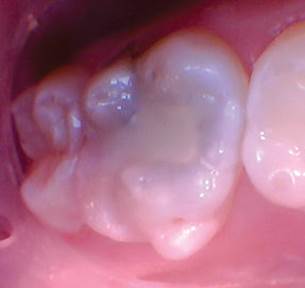

Caso 6

Una niña de 2 años presentó lesiones cariosas en todos sus molares primarios. Las opciones de tratamiento se discutieron con el cuidador principal del paciente, que incluyó: atención domiciliaria mejorada solamente, anestesia general para atención restaurativa o tratamiento con fluoruro de diamina de plata. El médico del paciente eligió el fluoruro de diamina de plata.

Figura 1. Presentación posterior a FDP de los molares primarios inferiores derechos que muestran lesiones detenidas.